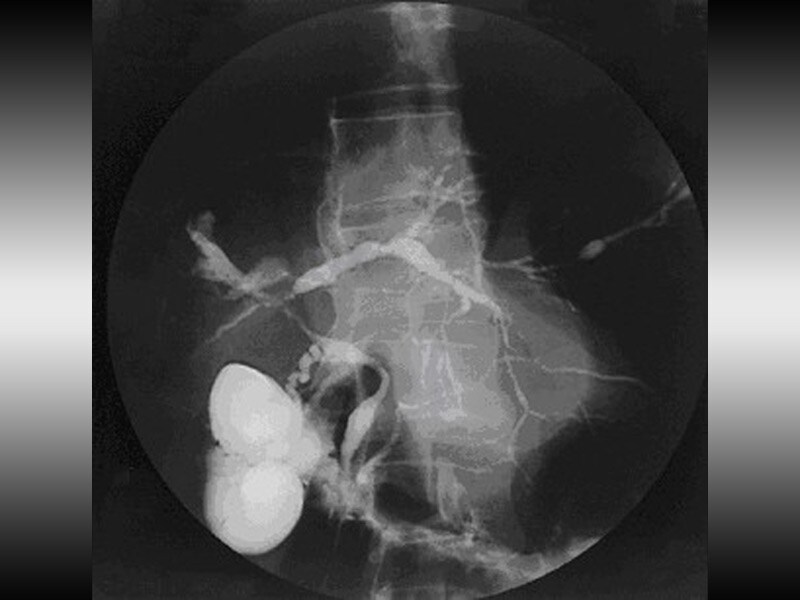

Фотографии и изображения, связанные с симптомами первичного склерозирующего холангита